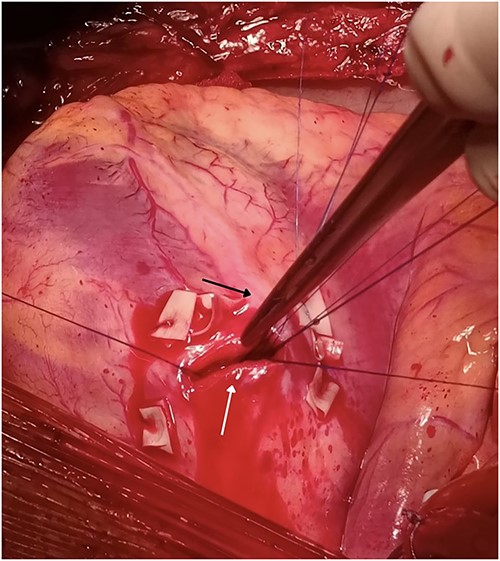

Our team performed urgent sternotomy, pericardiotomy and evacuation of hemopericardium, and only then was the full extent of the injury verified – a penetrating wound to the LV which measured ~2 cm and transected the second diagonal branch of LAD (Fig. 2). The knife missed the LAD by ~2 mm.

Penetrating wound to the LV measuring 2 cm (white arrow) missing the LAD (black arrow) by 2 mm but transecting the second diagonal branch of the LAD.